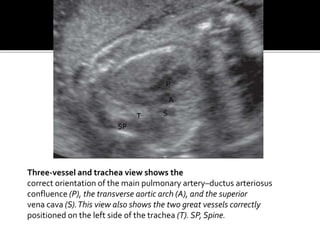

Three-vessel and trachea view shows the

correct orientation of the main pulmonary artery–ductus arteriosus

confluence (P), the transverse aortic arch (A), and the superior

vena cava (S).This view also shows the two great vessels correctly

positioned on the left side of the trachea (T). SP, Spine.

Three-vessel and tracheaview shows the correct orientation of the main pulmonary artery–ductus arteriosus confluence (P), the transverse aortic arch (A), and the superior vena cava (S).This view also shows the two great vessels correctly positioned on the left side of the trachea (T). SP, Spine. P A S SP T